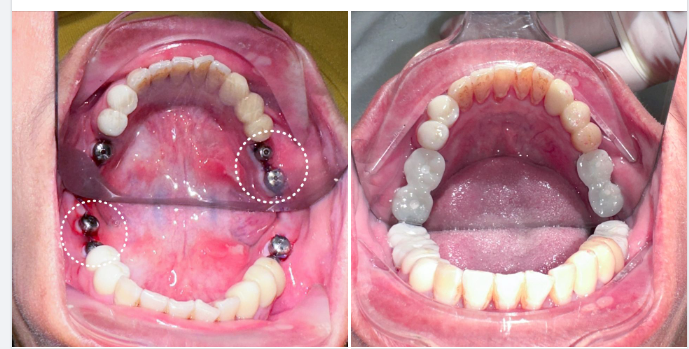

Trồng Răng Implant

Trồng Răng Implant -